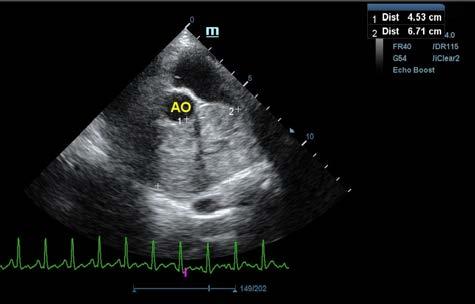

Se realiza ecocardiografía en la cual observamos engrosamiento de la válvula mitral (Fig. 2) y alteración de la estructura de las cámaras cardiacas: ratio atrio izquierdo/aorta 2,25 (Fig. 3), diámetro de ventrículo izquierdo en diástole normalizado (DVIdn) 1,98, patrón de flujo transmitral pseudonormal con velocidad máxima de onda E de 1,7 m/s, tiempo de relajación

M. López,1 V. Fernández,2 J. Engel3 1Servicio de cardiología y diagnóstico por imagen. 2Servicio de cirugía. Laclinicaveterinaria. c/Marroquina 26. 28030 Madrid. 3Servicio de cardiología. ANICURA-Benipeixcar Hospital Veterinario. Avinguda de la Constitució 68, bajo izq. 46009 Valencia. ANICURA-San Francisco Hospital Veterinario. c/ Sant Francesc 65. 12500 Vinaròs (Castelló). ANICURA-San Vicente Hospital Veterinario. c/ Veterinario Manuel Isidro Rodríguez García 17. 03690 San Vicente del Raspeig (Alicante). Figura 1. Radiografía lateral de tórax en la que se observa cardiomegalia generalizada, VHS 15. Patrón alveolar intersticial compatible con edema pulmonar. Patrón vascular mixto y patrón bronquial en lóbulos caudales, compatible con bronquitis crónica, mineralización por degeneración senil.

Figura 2. Ecocardiografía en corte paraesternal izquierdo eje largo, de 4 cámaras en la que se observa engrosamiento de la válvula mitral (flecha). Figura 3. Ecocardiografía en corte paraesternal derecho eje corto en base de corazón, visualizando ratio atrio izquierdo/aorta aumentado. Figura 4. Ecocardiografía en corte paraesternal izquierdo en base de corazón, en las que se observa la estructura hiperecoica y heterogénea junto a la aorta en un corte de la lesión transversal (A) y otro longitudinal (B). Compatible con neoplasia. A B Figura 5. Ecocardiografía en corte paraesternal izquierdo eje largo, optimizada para válvula tricúspide en la que se observa estructura hiperecoica.

La ecocardiografía es el método de elección para confirmar el diagnóstico de EDVM y estimar la severidad de la regurgitación mitral. Los hallazgos ecocardiográficos incluyen el engrosamiento y/o prolapso de las hojas mitrales junto con la identificación de la regurgitación mediante Doppler. Como se comprobó en el estudio post mortem en nuestro caso, a menudo se observan alteraciones en la válvula tricúspide, pero suelen ser menos marcadas que las de la válvula mitral.2 La ecocardiografía permite adquirir dimensiones del AI en relación con la aorta, o valoración del diámetro del VI en diástole y sístole, muy útiles para estimar el grado de remodelación (agrandamiento) cardíaco.2